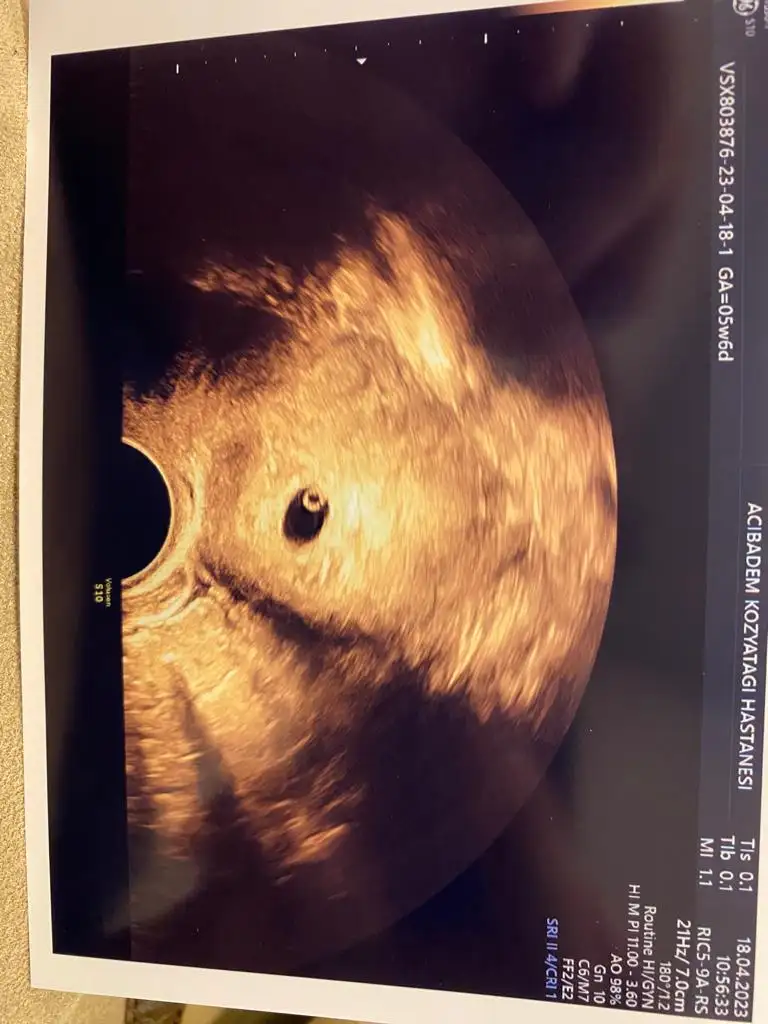

Canım benim Bugun tüp bebek transferinden sonra 20. Günüm burada yolk kesesi var mi anlayamadımCanım hani bebeğin eşi derler ya oyani bebeğin kordon oluşmadan önceki beslendiği yer, ilk başlarda kesenin içinde ufak bir kese daha oluşuyor sonra bebek büyüyüp kordon olustukca yolk kesesi küçülüyor. Yolk kesesini görmek boş gebelik olmadığını ve bebeğin kalbinin atmaya başlayacağını gösteren de bir şey o yüzden herkes oh yolk kesesini gördük diyor

Masallah onaCanım benim Bugun tüp bebek transferinden sonra 20. Günüm burada yolk kesesi var mi anlayamadım